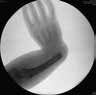

Am Ellenbogen wird die aktive und passive Beuge- und Streckfähigkeit beurteilt und die Unterarm-Umwendung im proximalen Radio-Ulnargelenk geprüft. Bei einer Ellenbogenaplasie kann die Bewegung am Ellenbogen aufgehoben, aber ein vollständiger Faustschluss möglich sein (Abb. 2a–c). Die Greiffunktion bei einer Symbrachydaktylie vom Spalthand-Typ kann auch mit zwei aktiv beweglichen Fingern, die aufeinander ausgerichtet sind, für einen 2‑Punkt-Griff sehr gut geeignet sein (Abb. 3a u. b). Bei einer Peromelie (Abb. 4) kann eine Transplantation von zwei Zehen zur Schaffung eines Spitzgriffs 8 führen. Wird dies nicht gewünscht, kann eine (myoelektrische) Prothesenversorgung mit den Eltern besprochen werden. Ein Therapieziel kann die Schaffung einer fünfstrahligen Hand sein, z. B. bei numerischen Fehlbildungen wie einer Hexadaktylie (Abb. 5) oder einer Doppeldaumen-Anlage. Ein weiteres wichtiges Therapieziel ist die Schmerzreduktion. Bei einem Schnürfurchen-Syndrom können im Wachstum Schmerzen auftreten; es besteht die Gefahr einer knöchernen Durchspießung (Abb. 6).